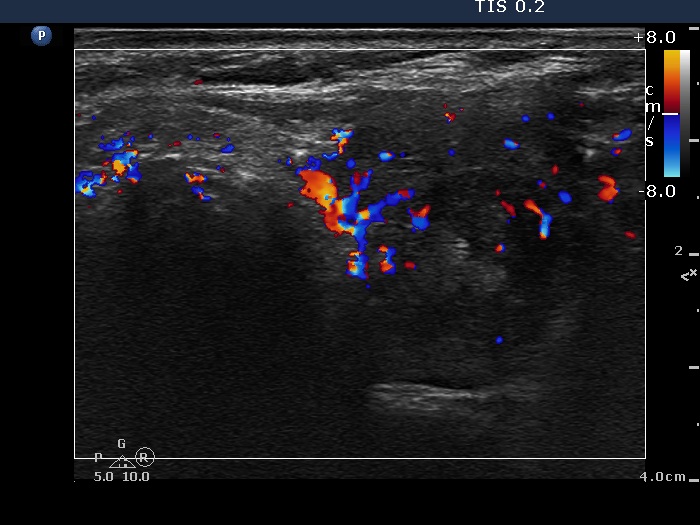

Graves' disease - case 1147

Follow-up investigation 6 months after first visit (ultrasonographic picture 6)

Right lobe, transverse scan, color Doppler mode. The vascularization is average or a slightly increased.